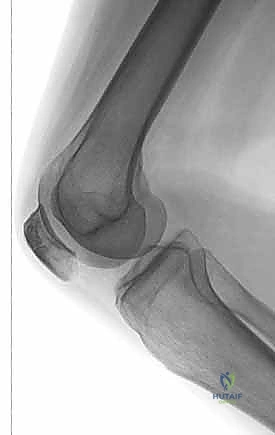

الأشعة السينية (X-rays): هي الخطوة الأولى والأساسية. يتم أخذ صور من زوايا متعددة:

- المنظر الأمامي الخلفي (AP View): لتقييم النمط العام للكسر.

- المنظر الجانبي (Lateral View): حاسم جداً لتقييم مدى تباعد أجزاء الكسر (Displacement) وعدم انتظام السطح المفصلي (Articular step-off).

- منظر السماء (Skyline View): مفيد لرؤية الكسور الطولية وتقييم التمفصل بين الرضفة وعظم الفخذ، ويتم إجراؤه إذا كانت حالة المريض تسمح بثني الركبة قليلاً.